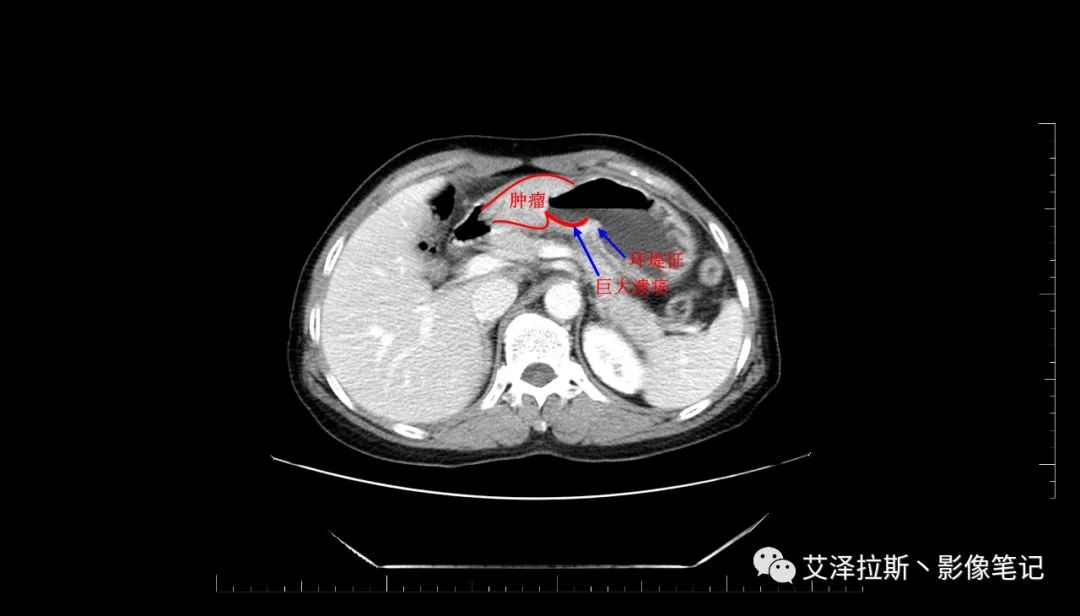

圖2 腫瘤

【影像所見】 胃竇部狹窄,胃壁環形增厚,小彎側見一巨大潰瘍,周圍伴“環堤征”,漿膜面不完整,胃周脂肪見網格狀條索影,病灶與肝臟左葉、胰腺鉤突脂肪間隙消失,增強掃描病灶明顯強化。引流區內約15個區域淋巴結受累。

【診斷意見】 胃竇部胃癌(T4N3期) 該病例腫塊突破漿膜層,與肝臟左葉、胰腺鉤突分界不清,脂肪界面消失,定為T4期; 受累及的淋巴結為15個區域,定為N3; 有無遠處轉移尚不明確,所以M期暫時無法確定。